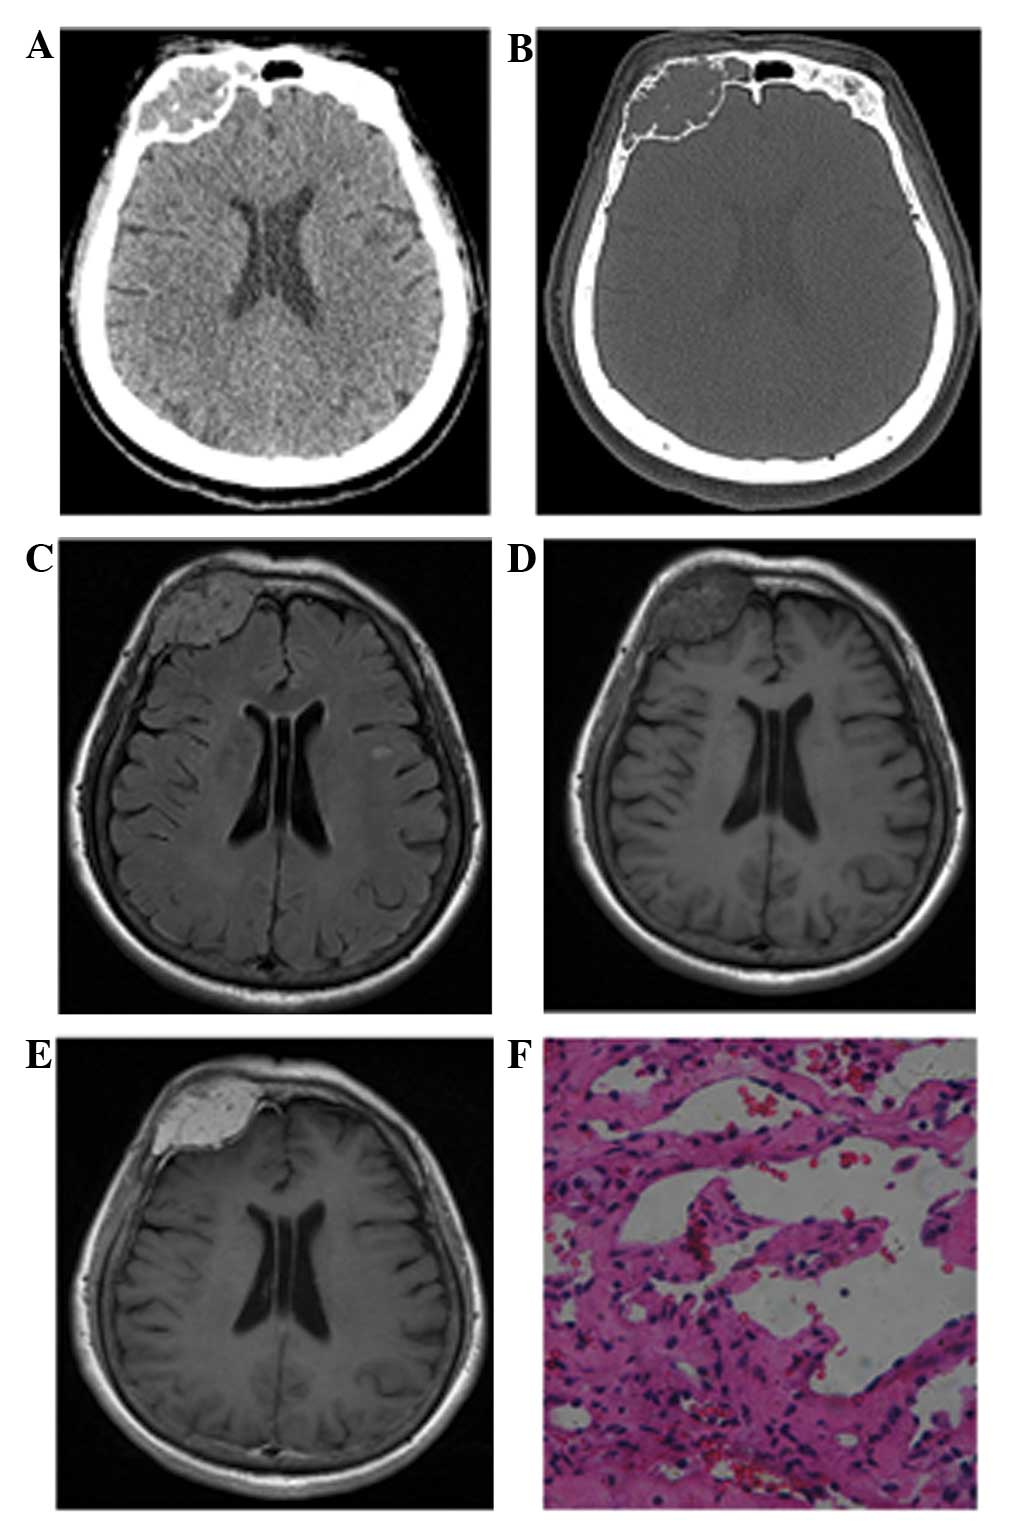

The neuroradiological findings of the HEs are summarized in Table I. While 2 cases exhibited lesions in the right side of the skull, 1 in the frontal bone (Fig. 1) and the other in the parietal bone, another 2 cases presented with lesions in the tentorium. Moreover, 1 case presented with a lesion in the cerebral falx, 1 case with a lesion in the right cavernous sinus and 1 case with a lesion in the right temporal lobe (Fig. 2). CT and MRI results showed that 2 masses were round (Fig. 1), whereas the remaining 5 tumors were lobulated. The total diameter ranged between 2.1 and 5.3 cm. The 3 patients who underwent CT presented predominantly with isoattenuation, with radiodensity values ranging from 32–47 HU, and a dotted calcification was detected in 1 lesion (Fig. 2A). The 2 lesions originating from the skull showed local bone destruction and osteolysis. The cortical bones were discontinuous with sclerotic margins, and exhibited soft-tissue density and spine-like protuberances (Fig. 1A). Moreover, 1 case occurred in the right frontal bone and involved the superior edge of the right orbit and frontal sinus.

Figure 2.

Case 3: A 57-year-old woman with hemangioendothelioma. (A) Axial computed tomography image showing a well-defined high-density mass with a calcified nodule in the right temporal lobe. (B) The lobulated mass is heterogeneous and hyperintense in the axial T2-weighted image, with moderate peritumoral edema. (C) Axial T1-weighted image showing multiple high-intensity dots that reflect hemorrhage and thromboses. (D) Contrast-enhanced axial T1-weighted images showing heterogeneous multi-nodular enhancement.

The MRI images of the 7 lesions were primarily isointense (n=5) or mildly hypointense (n=2) compared with the gray matter on T1-weighted images. All tumors were scattered hyperintensely due to intratumoral hemorrhage (Figs. 1D, 2C, 3A and 4A). T2-weighted and FLAIR images showed that all tumors were inhomogeneously hyperintense to the cortex. Mild or moderate peritumoral edema was noted in 4 cases, whereas no evident edema signals were observed in the 2 cases with skull lesions and in the case with a lesion in the right cavernous sinus (Fig. 4). The lesions exhibited a lobulated and septated appearance due to the coalescence of multiple high-signal nodules within the tumor (Fig. 2B). The signal voids in the vessels were also visible in all cases (Figs. 1C, 2B and 4B). DW imaging (b=1,000) showed that 6 tumors were hypointense, whereas 1 tumor was inhomogeneous with high-low mixed signal compared with that of the white matter (Fig. 3B).

Contrast-enhanced T1-weighted images showed contrast enhancement in all tumors. All lesions exhibited inhomogeneous enhancement consisting of multiple nodules with relatively homogeneous enhancement compared with the surroundings in the early stage; such nodules became hyperintense with delayed enhancement. Additionally, 4 cases demonstrated a marked enhancement, called the ‘dural tail sign’ in the dura adjacent to the tumor. MRA also revealed ectopic vessels in the basilar region in 1 case (Fig. 4C).